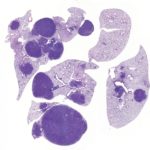

Immagine, le cellule non senescenti sono state mostrate con colori diversi. A destra: le cellule senescenti apparivano spesso con più nuclei blu e non sintetizzavano il DNA. Credito: Università della California del sud.

Scott Fraser e il suo laboratorio hanno lavorato con il team di ricerca per sviluppare immagini 3D dei risultati. Le immagini hanno rivelato inaspettatamente che le cellule senescenti hanno spesso due nuclei e che non sintetizzano il DNA.